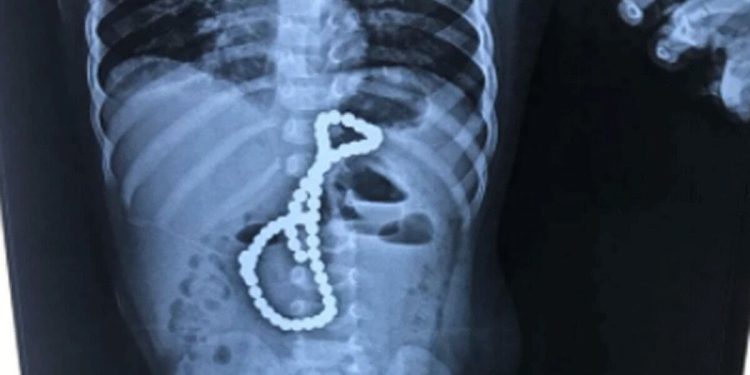

बच्चे को लगातार उल्टी और डिहाइड्रेशन की शिकायत हो रही थी. डॉक्टरों ने फौरन एक्सरे करवाया. एक्सरे में डॉक्टरों को पेट में माला जैसा कुछ दिखा. बच्चे के परिजनों में घर पर ऐसी किसी माला के होने से इनकार किया. इलाज के लिए डॉक्टर ने परिजनों से ऑपरेशन की बात कही|

डॉक्टर्स के लिए यह ऑपरेश काफी मुश्किल था. जब बच्चे के पेट में चीरा लगाया तो उपकरण उसमें चिपकने लगे. जिसके बाद चुंबक की गोलियां होने की जानकारी मिली. फिर लोहे के उपकरण से चुंबक की खोज की गई. चुंबक की यह गोलियां आंतों में आपस में चिपकी हुई थीं |

अस्पताल की एचओडी डॉक्टर समायरा खान ने बताया कि सबसे बड़ी चुनौती चुंबक की 65 गोलियों को एक-एक करके पेट से निकालने की थी. गोलियों ने आपस में चिपक कर माला का रूप ले लिया था. डॉक्टरों ने 5 घंटे के सफल ऑपरेशन के बाद बहुत सावधानी से बच्चे के पेट से चुंबक की गोलियों को निकाला |